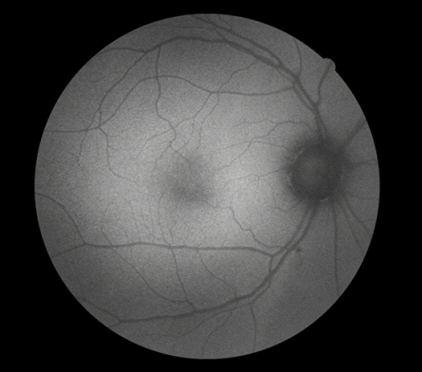

ICGA主要用于觀察脈絡(luò)膜的血管結(jié)構(gòu)和循環(huán)特點,揭示脈絡(luò)膜循環(huán)的細(xì)節(jié),是目前PCV診斷的“金標(biāo)淮“。且由于吲哚青綠染料具有與熒光素鈉不同的特性,所以能更加直觀地了解脈絡(luò)膜血管循環(huán)狀態(tài),可彌補FFA檢查看不清脈絡(luò)膜循環(huán)的不足,在某些特殊情況下可協(xié)助FFA對視網(wǎng)膜血管性疾病診斷作出補充。

ICGA影像